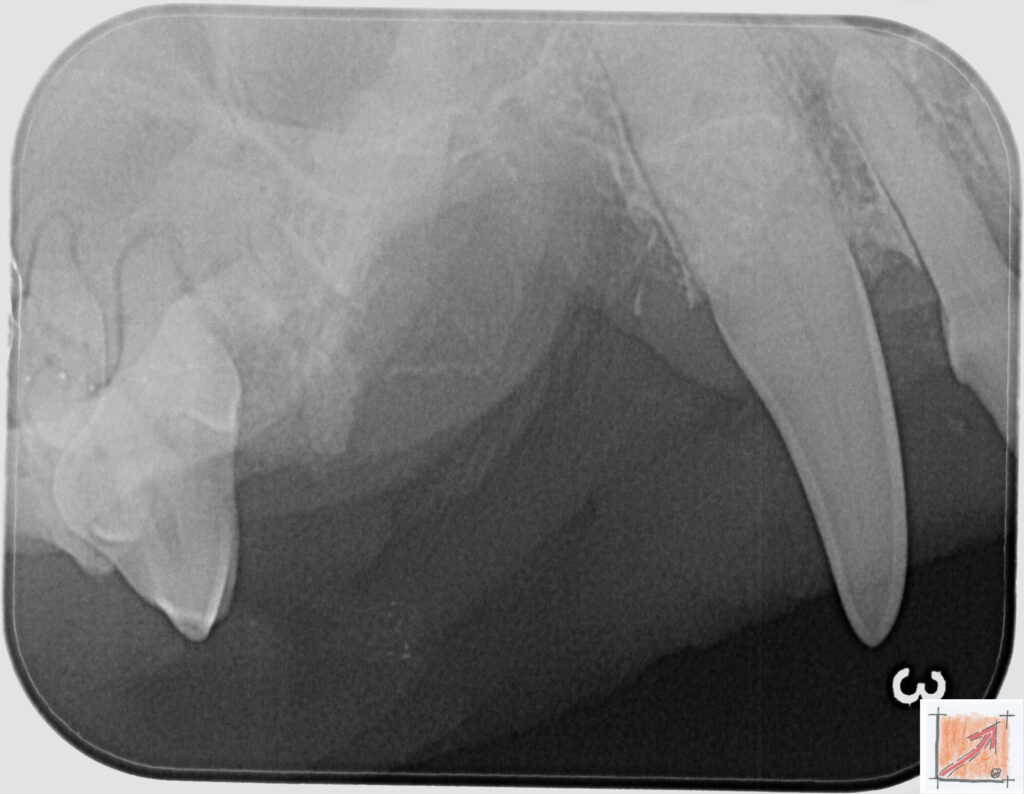

Röntgenbilder vom Thierrischen Orakel bei der Zahn-OP:

Warum Dentalröntgen beim Chihuahua lebenswichtig ist:

Ein Blick hinter die Kulissen von Chihuahua-Zähnen:

In dieser Galerie zeigen wir exklusive intraorale Röntgenaufnahmen einer Zahn-Operation beim Thierrischen Orakel als Chihuahua vom BauFachForum. Während oberflächlicher Zahnstein oft sichtbar ist, verbirgt sich die wahre Gefahr für das Herz meist unter dem Zahnfleischsaum.

Das digitale Dentalröntgen ist der Goldstandard in der modernen Tiermedizin, um parodontale Entzündungsherde und Wurzelabszesse sicher zu diagnostizieren. Für Chihuahuas wie dem Thierrischen Orakel, mit Mitralklappeninsuffizienz ist dieser diagnostische Schritt essenziell. Nur wenn versteckte Bakterienherde an der Zahnwurzel oder mit dem Fachbegriff Apikalabszesse erkannt und saniert werden, kann das Risiko einer bakteriellen Endokarditis oder einfach ausgedrückt einer Herzinnenhautentzündung minimiert werden.

Unsere Aufnahmen von Patienten dem Thierrischen Orakel verdeutlichen den Unterschied zwischen einer rein optischen Zahnreinigung und einer medizinisch fundierten Sanierung unter Röntgenkontrolle.

Chihuahua Mitralklappeninsuffizienz Trachealkollaps:

Wichtig ist im Vorfeld die Zahnhygiene des Chihuahuas. Die Bilder zeigen Dentale Röntgenbilder vom Thierrischen Orakel als Chihuahua-Hund während seiner Zahn-OP. Darstellung von Kieferknochen und Zahnwurzeln zur Diagnose von Parodontitis.

Zahnröntgenaufnahme bei Chihuahua Thierry:

Untersuchung der Zahnwurzeln auf Entzündungsherde als Prophylaxe gegen bakterielle Endokarditis.

Intraorales Dentalröntgen eines Chihuahuas:

Die Bilder zeigen Zähne und Wurzelstrukturen im Unterkiefer zur Planung einer Extraktion bei hochgradigem Zahnstein.